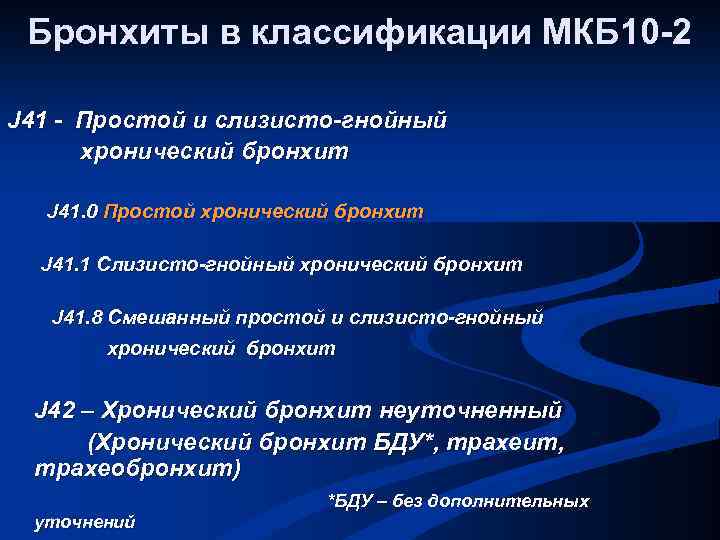

Бронхиты в классификации МКБ 10 -2 J 41 - Простой и слизисто-гнойный хронический бронхит J 41. 0 Простой хронический бронхит J 41. 1 Слизисто-гнойный хронический бронхит J 41. 8 Смешанный простой и слизисто-гнойный хронический бронхит J 42 – Хронический бронхит неуточненный (Хронический бронхит БДУ*, трахеит, трахеобронхит) уточнений *БДУ – без дополнительных